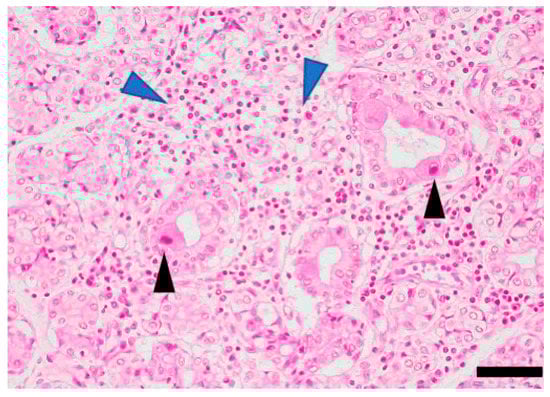

- Fleck, M.; Kern, E.R.; Zhou, T.; Lang, B.; Mountz, J.D. Murine cytomegalovirus induces a Sjogren’s syndrome-like disease in C57Bl/6-lpr/lpr mice. Arthritis Rheum. 1998, 41, 2175–2184. [Google Scholar] [CrossRef]

- Ohyama, Y.; Carroll, V.A.; Deshmukh, U.; Gaskin, F.; Brown, M.G.; Fu, S.M. Severe focal sialadenitis and dacryoadenitis in NZM2328 mice induced by MCMV: A novel model for human Sjogren’s syndrome. J. Immunol. 2006, 177, 7391–7397. [Google Scholar] [CrossRef] [PubMed]